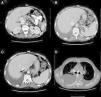

At his admission, increase of lower limbs oedemas was evidenced, in addition to scrotal and abdominal wall oedema. Diuretic treatment was initiated with partial improvements. At admission, the analytical test (Table 1) showed emphasised leukocytes persistence, elevation of acute phase reactants, hypoproteinemia and hypoalbuminemia, and normal hepatic and renal function. Autoimmunity study (anti-nuclear antibodies, extractable nuclear antibodies, anticytoplasmic antibodies, rheumatoid factor, anti-citrulline antibodies), blood cultures, viral serology for hepatitis B and C, and human immunodeficiency virus resulted negative. The echocardiogram showed a minimum pericardial effusion, without signs that suggest constriction. An abdominal Doppler echography confirmed the presence of homogeneous hepatomegaly and mild ascites. No flow in middle and left suprahepatic veins (Budd-Chiari syndrome). Right suprahepatic vein was partially permeable with monophasic flow and the caudal vena cava was slightly enlarged. Also, there was evidence of portal hypertension signs with collateral circulation in the splenic hilum, retroperitoneal and umbilical vein repermeabilisation. These findings have been confirmed with an abdominal tomography (Fig. 2A–C). Urinalysis showed a urine protein of 0.1g/24h. Due to the presence of hypoproteinemia, hypoalbuminemia and vitamin deficit, a malabsorption syndrome was suspected. The results of serum transglutaminase test were also normal. Subcutaneous abdominal fat biopsy was performed and there was no evidence of amyloid material. Colonoscopy and ileoscopy excluded the presence of ileitis. Intestinal lymphangiectasia was suspected due to portal vein hypertension, splanchnic and protein-losing enteropathy, and was confirmed with the elevated excretion of alpha-1 antitrypsin in stool (2.85mg/g reference value <0.3) and compatible images found with capsule endoscopy in the duodenal tract (Fig. 1D). During hospital stay, the patient experienced recurrent episodes of thrombophlebitis, consequently requiring a central line (femoral) inserted at 72h. As it was not possible to administer an intravenous treatment, a central line was inserted using arteriogram, evidencing great collateral supraclavicular circulation and in thorax (Fig. 2D). Internal jugular vein was reduced and external jugular vein was dilated; thrombosis of both innominate trunks with abundant collateral circulation which drained to the pericardiacophrenic vein was observed by means of the contrast injection. Such a vein was catheterised, where a bicameral subcutaneous reservoir was inserted, which the patient could only tolerate for 24h because of pain during drug administration.